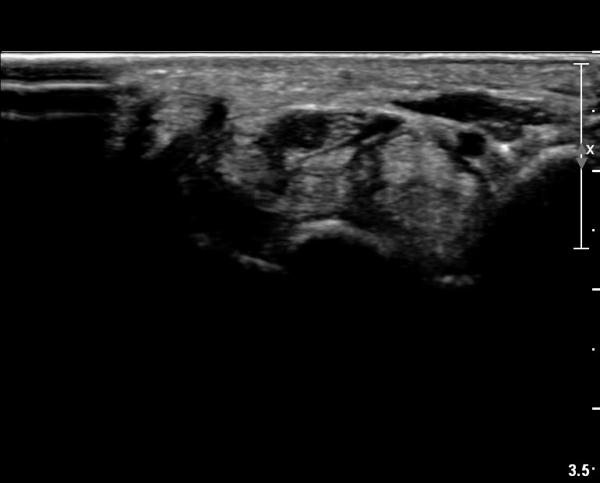

ÃÊÀ½ÆÄ ¼Ò°ß :  ¼Õ¸ñ±ÙÀ§ºÎ Ⱦ´Ü¸é°Ë»ç¿¡¼­ ¼Õ¸ñ±¼±Ù°Ç(FCR)°ú Ç¥Ãþ ¼Õ°¡¶ô ±ÁÈû±Ù(FDS) »çÀÌ¿¡

Á¤Á߽ŰæÀÌ Á¤»óÀûÀÎ ¾ç»óÀ¸·Î º¸ÀÓ(»çÁø 1).

Å½ÃËÀÚ¸¦ ¸»´ÜÀ¸·Î À̵¿ÇÏÀÚ  Á¤Áß½Å굥 ¿äÃø ÀϺΰ¡ Àú¿¡ÄÚ Á¾±«·Î °üÂûµÊ(»çÁø 2).

ÀÌ·± ¸ð½ÀÀº ¼Õ¸ñÀÇ ¿ù»ó°ñ ºÎÀ§(»çÁø 3, 4)¸¦ Áö³ª ¼ö±Ù°ü ±ÙÀ§ºÎ ±îÁö À̾îÁü(»çÁø 5).